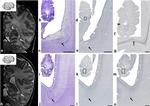

Ki-67 Antibody in Immunohistochemistry (Paraffin) (IHC (P))

Ki-67 Antibody in Immunohistochemistry (IHC)